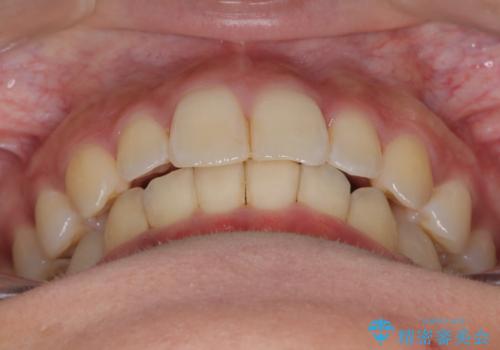

ディープバイト改善のためのインビザライン治療

- 患者様は、全体的な歯列のガタガタとディープバイト(深い噛み合わせ)を主訴として来院されました。診断の結果、ディープバイトを改善するためには、歯列全体の拡大が必要であると判断しました。治療には、透明なマウスピース型矯正装置「インビザライン」を使用し、歯を適切に拡大しながら歯並びを整える計画を立てました。治療期間はおおよそ2年を見込んで進め、最終的に見た目にも大きく変化をもたらすことを目指しました。

ディープバイトの治療には、奥歯の高さや前歯の位置に対する繊細な調整が必要です。本症例では、インビザラインによる歯列拡大を行うことで、噛み合わせを改善し、歯並び全体を整えました。治療過程では、歯間のスペースを確保するため、IPR(インタープロキシマルリダクション)を適宜行い、無理なく歯列の調整を行いました。治療後は、歯並びが大きく改善され、患者様の見た目にも大きな変化が現れました。インビザラインは透明で目立たず、治療中の見た目を気にされる患者様にも配慮した治療法です。